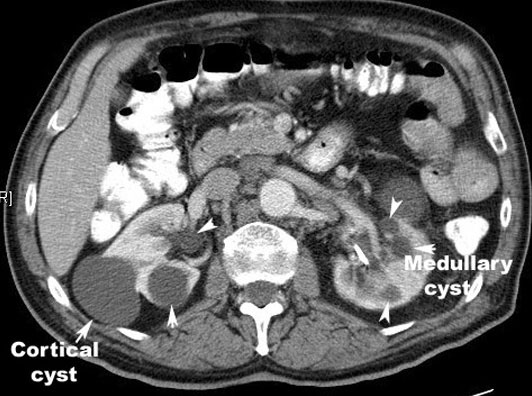

Multiple Renal Cysts

Characteristics of simple renal cyst:

- Round

- Thin walled

- Smooth interior

- Filled with clear liquid

- Does not enhance with contrast